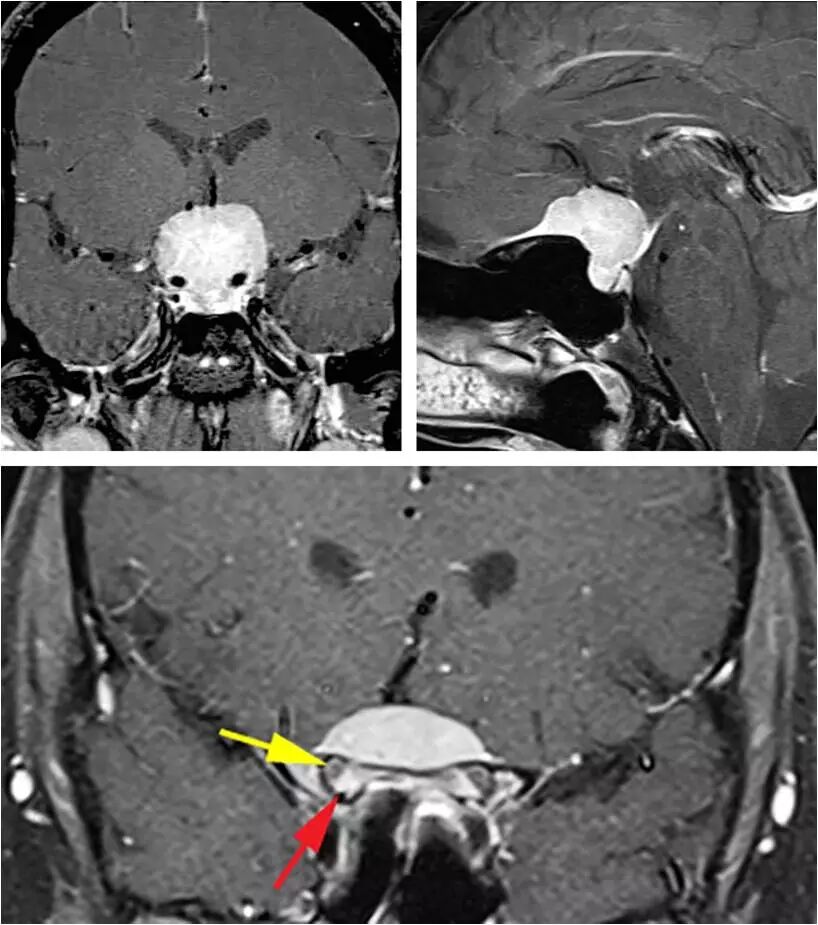

图2. 这例典型的鞍结节脑膜瘤体积大并且挤压、包绕血管,因此最适合经颅切除,而不是经鼻。肿瘤的影像学表现也非常具有特征性:鞍内不扩大(左上图)和额底可见脑膜尾征(右下图)。下图提示病变已经累及双侧视神经管,而且以右侧为甚。红色箭头指的是视管内强化的肿瘤,黄色箭头则是指被移位的视神经。